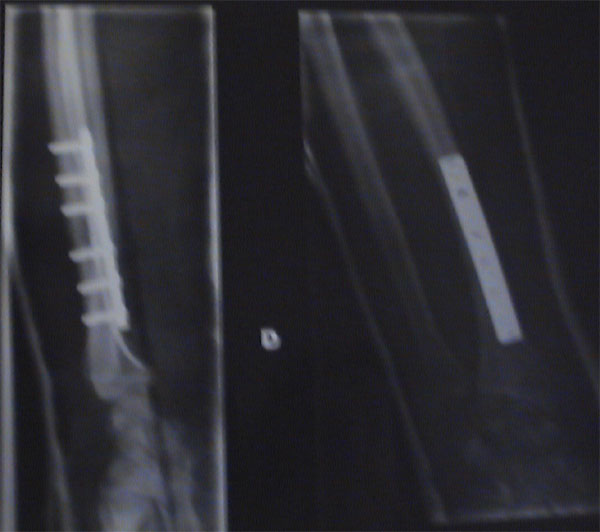

je tiens a remercier tout particulièrement les gens du Centre Hospitalier de Grenoble ki m’ont offert une magnifique plaque en fer et 6 vis pour mon bras ainsi qu’un superbe platre blanc !!

et comme y font pas les choses a moitié a grenoble, j’ai même eu la petite écharpe assortie pour porter le tout

jvous mettrai les fotos de mes cadeaux demin

Bien réparé en tout cas Sont bon au centre hospitalier de grenoble